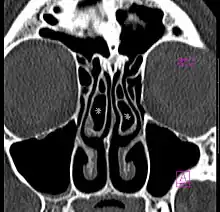

Concha bullosa bilatérale en scanner (coupe coronale)

Il s'agit d'une variante anatomique fréquente, retrouvée chez près de la moitié de la population[2]. Elle est bilatérale dans la moitié des cas[2].

La présence d'une concha bullosa est associée de façon significative à une déviation controlatérale du septum nasal[2].